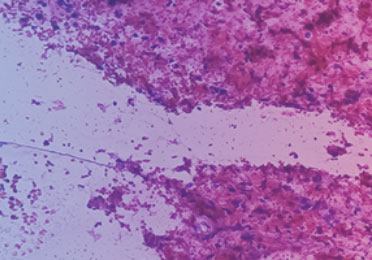

Um eine bösartige Erkrankung zu bestätigen, ist die Untersuchung einer Tumorgewebeprobe entscheidend.